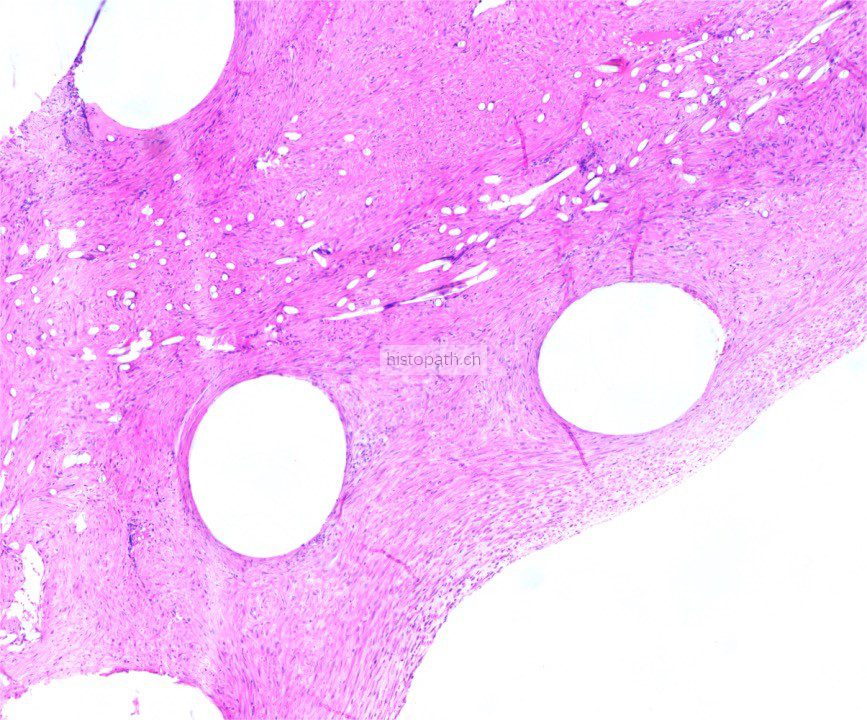

使用德国EXAKT切磨系统进行硬组织切片,特别是对于含有金属这类植入物的组织,是一种精确的组织切片技术。

各类尺寸的含金属植入物骨、牙齿、血管等硬组织样本脱水,7200树脂浸润包埋,后期用标准尺寸(25mm*75mm)的树脂片进行切磨片处理。

将包埋好的硬组织树脂块,用EXAKT 硬组织切片机先切一个200um的厚片,然后再通过EXAKT 硬组织磨片机将其磨到20-30um薄片,样本是已经硬组织包埋好的含金属的动物样本。

针对不同的病理阅片指标需求,行HE染色、Masson染色、亚甲基蓝-酸性品红染色、VG染色、Movat染色等。